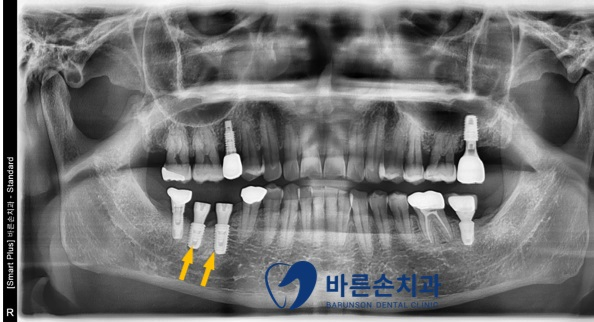

우측 아래 임플란트 2개(노란 화살표)가

임플란트 주위염으로 인해

치조골이 내려가 있습니다.

임플란트를 제거하고,

치조골이 내려간 부분에 뼈를 다시 만들고

다시 임플란트를 식립하기로 합니다.